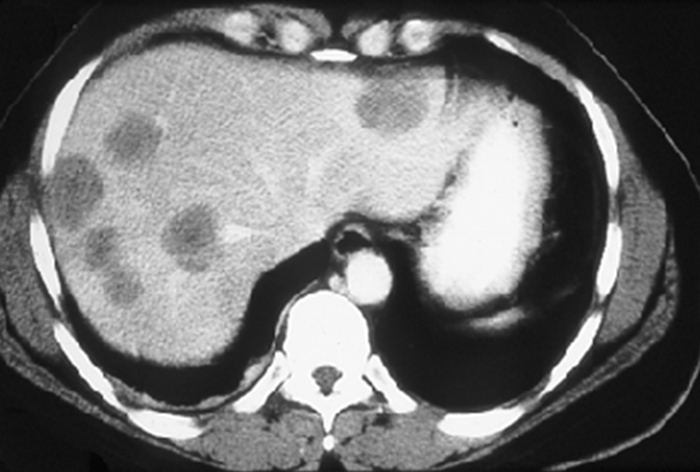

Liver Mets Diagnosis

This patient with weight loss and fatigue has multiple liver lesions on CT scan, suggesting metastatic disease to the liver rather than primary liver cancer. Colorectal cancer is the most common source of liver metastases (as blood from the colon moves through the portal circulation directly to the liver) and should be excluded in this patient, even in the absence of specific symptoms (eg, alteration in bowel habits, gastrointestinal bleeding). Abdominal CT is a useful screening test but can often miss primary intraluminal tumors. Colonoscopy is the most appropriate next diagnostic step as it both localizes the tumor and provides a tissue diagnosis.